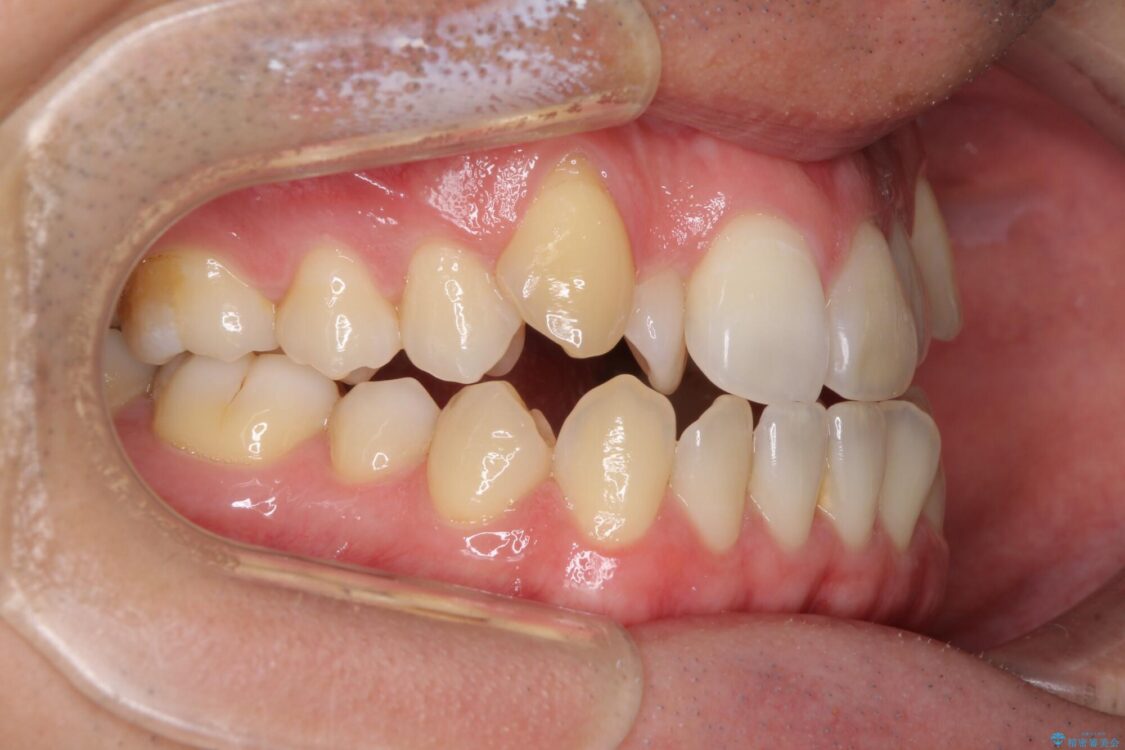

八重歯と前歯のデコボコを気にして来院された患者様です。

治療前

• 左右の八重歯が気になる ワイヤー装置での咬み合わせ改善 治療前画像